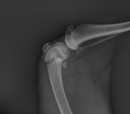

Sweet Wyatt was picked up and brought to CVRC in Charleston, SC.  He has a distal fracture of his left femur that is not significantly displaced but will need to be stabilized.  He also has a right femur fracture up by the pelvis, which will require an FHO (Femoral Head Ostectomy) or an amputation.  Wyatt has fractures at the two worst places where there are not a lot of room to work.  One by his pelvis, and the other next to his knee.  The other issue is he was very anemic from loss of blood and parasite over-load.  Both of these issues had to be addressed before he could have surgery.

While Wyatt was being stabilized, it was determined he had an old injury to his pelvis before being hit by a car. His right hip area had extensive muscle loss.  Dr. Rachel Seibert did a thorough Wyatt examination before taking him into surgery to do the two repairs.  Once Wyatt was on the table and surgery had begun, it became apparent these were old injuries, and remodeling had begun.  Dr. Seibert had to break down the callused areas to get clean bones to join.